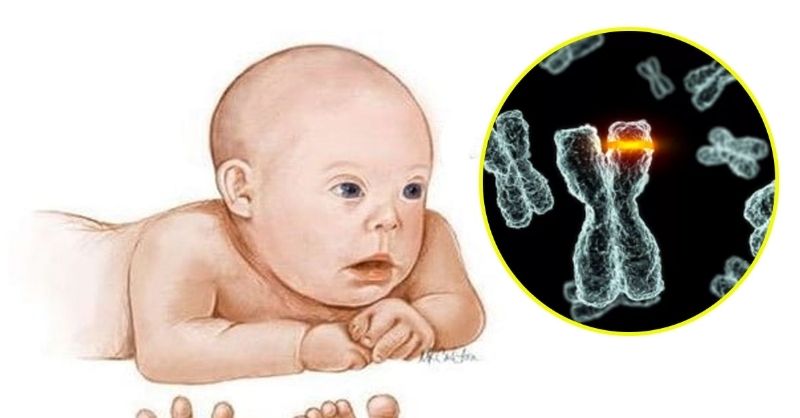

Japanese scientists delete chromosome that causes down syndrome